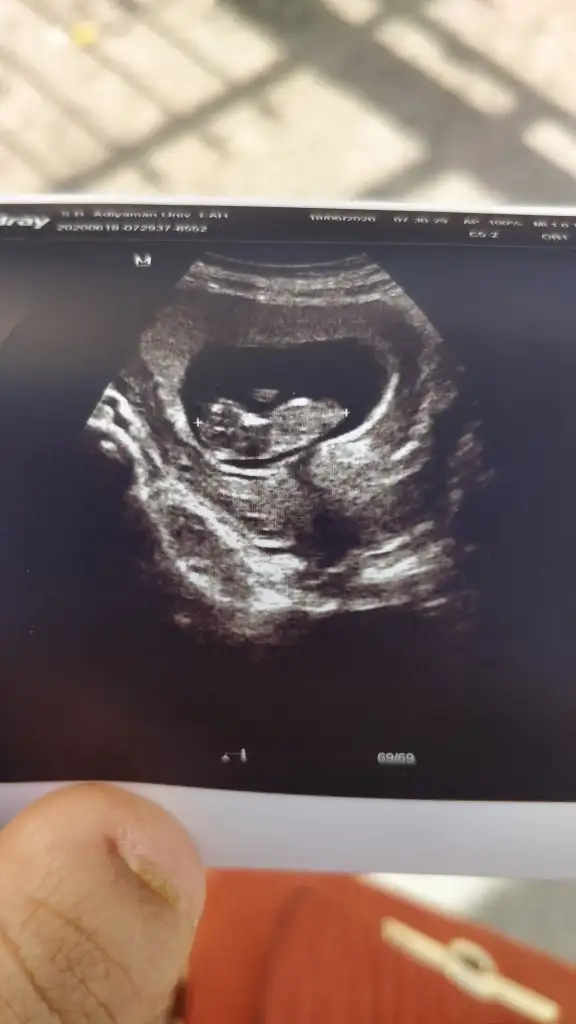

Şimdiki usg ni atsana canımIkra meyra M mely15 bana erkek gibi demiştiniz doktor kız dedi çok az baktı ultrasonda yanılmış olabilir mi doktor

Banada bakarmısınızben erkek demistim yada kizmi unutum erkekti galiba vallah merak ettim simdi banada kim beni görse erkek diyo burdaki arkadaslar kiz dediler galiba.ay sonu beli olcak insallah

Inşallah hayırlısı ile gelsin teşekkür ediyorum cevap v3rdiginiz için nerden anladiniz acaba bilgi verirmisiniz bi çıkıntı var yukarı doğru orasımi nubu acabaErkek olabilir